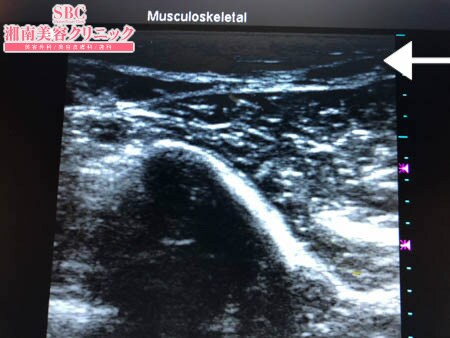

No.206037【脂肪吸引】【動画あり】湘南美容外科脂肪吸引最高責任者である竹田先生による脂肪吸引のフォトギャラリー!スタッフさんからの手術のご依頼は何よりも信頼の証!他院で取り残された二の腕の皮下脂肪をもうひと絞り!術中3Dタッチビュー・右ちからこぶ

皮下脂肪の取り残しがある、、、

ということで今回再手術することに。

決して多くはないものの

皮下脂肪の取り残しを徹底的に

根こそぎ!!

吸引しておきましたので